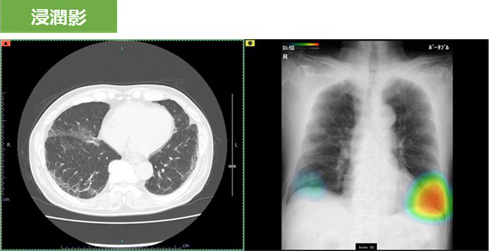

撮影した胸部レントゲン画像を自動解析して病変が疑われる領域を検出し、その部分をハイライトします。その領域を医師が再確認することで、見落し防止を支援します。

肺疾患の主要な画像所見となる「結節・腫瘤影」、「気胸」、「浸潤影」を検出することができます。